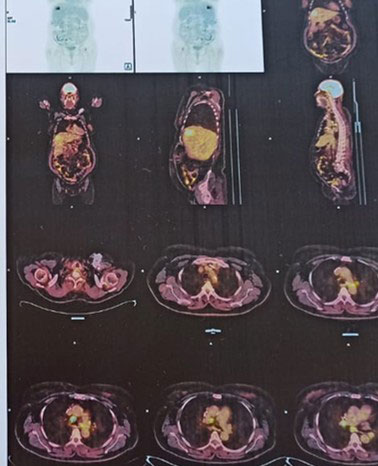

Radiology-

PET-CT revealed an FDG avid (SUV max 10.3), poorly circumscribed heterogeneous mass lesion measuring approximately 4.0 × 5.4 cm in the subcapsular region of segment VIII of liver with associated intralesional calcific foci. Background liver showed features of chronic liver disease with fatty change.

MRI Upper Abdomen: Mixed signal intensity lesion in segment VIII of liver which shows T2 hypointense component and T2 intermediate soft tissue signal intensity component.